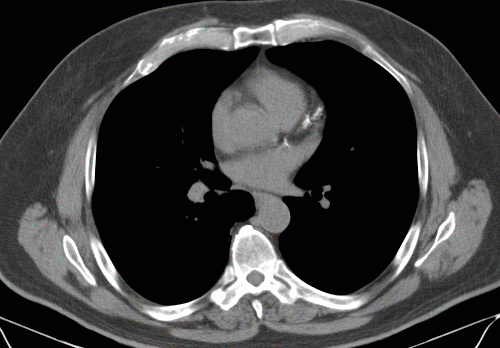

A Hounsfield annotációs eszköz létrehoz egy vizsgált területet, és kiszámítja annak átlagos pixelértékét és szórását.

Egy képterület Hounsfield-értékének megállapításához:

Válassza a Hounsfield-érték ikont

Kattintson a vizsgált területre

Húzza az egeret a terület meghatározásához

Engedje el az egérgombot

A képre rajzolt alapértelmezett vizsgált terület egy teljes kör. ROI átméretezése során a teljes kört a sarkakon található fogópontokkal tarthatja fenn.